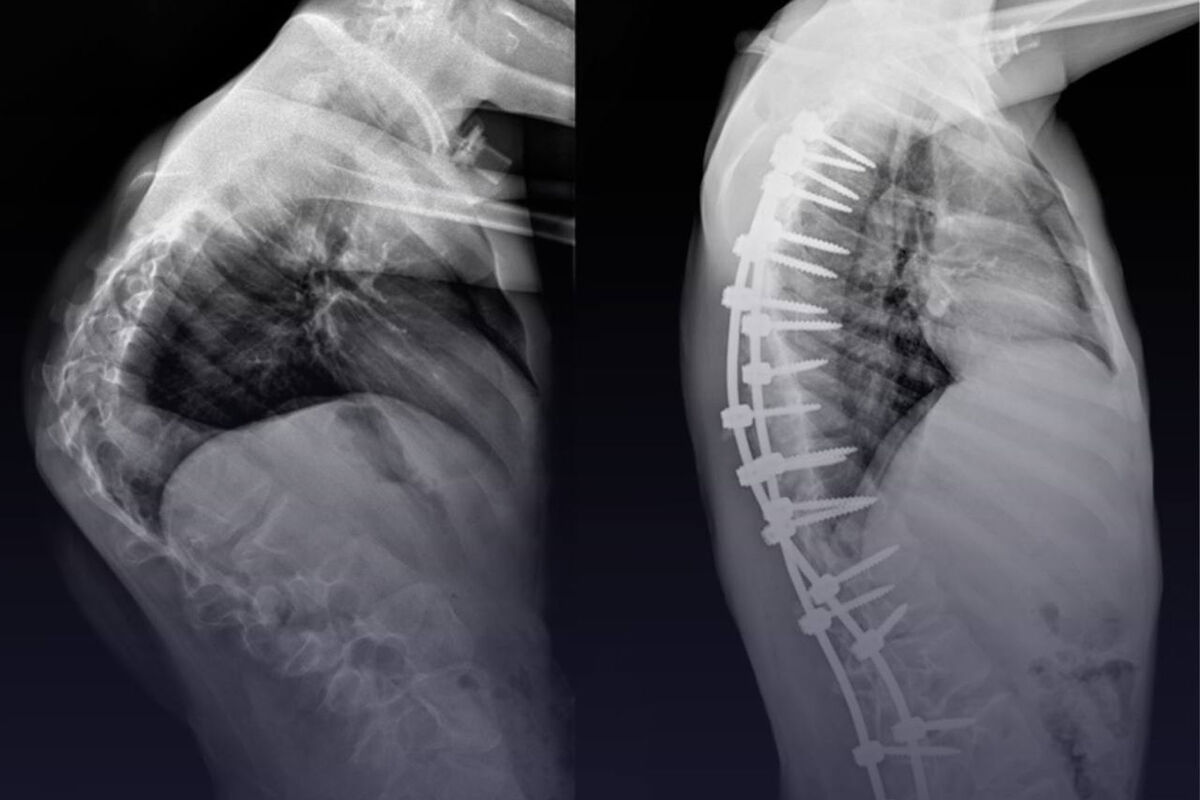

В Москве врачи семь часов оперировали ребенка со «скрученным» позвоночником

Хирурги отделения травматологии и ортопедии Российской детской клинической больницы имени Пирогова впервые в мире провели сложнейшую операцию ребенку, выпрямив ему «скрученный» позвоночник. Об этом сообщает пресс-служба Минздрава России.

13-летний мальчик длительное время находился под наблюдением врачей, проблемы с позвоночником начались у него около двух лет назад. У мальчика диагностировали синдром Протея — редкое генетическое заболевание, которое провоцирует разрастание тканей и деформирует позвоночник. В медицинской практике описано лишь 200 подобных случаев. Было принято решение о сложнейшем хирургическом вмешательстве.

«Сложность заключалась в степени деформации. Из-за выраженных гипертрофических изменений позвонков пришлось прибегнуть к обширному частичному удалению некоторых костных структур, а также трех ребер, чтобы улучшить адаптацию органов грудной клетки после операции», — рассказал хирург-вертебролог отделения травматологии и ортопедии Андрей Пантелеев.

Патологию удалось скорректировать, врачи обещают, что после курса реабилитации качество жизни пациента улучшится.